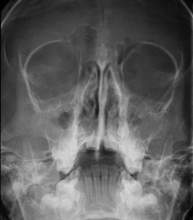

- RX Cráneo

Técnica mediante la cual, utilizando rayos X, se obtienen imágenes del cráneo para su estudio. Indicaciones: traumatismo, cierre precoz de suturas craneales. - RX Senos Paranasales

- Paranasal Sinuses X-ray

This technique uses X-ray rendered imaging for examining the paranasal sinuses. Indicated for: headache, chronic cough.